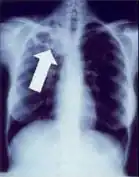

In active pulmonary TB, infiltrates or consolidations and/or cavities are often seen in the upper lungs with or without mediastinal or hilar lymphadenopathy or pleural effusions ( tuberculous pleurisy). However, lesions may appear anywhere in the lungs. In disseminated TB a pattern of many tiny nodules throughout the lung fields is common - the so-called miliary TB. In HIV and other immunosuppressed persons, any abnormality may indicate TB or the chest X-ray may even appear entirely normal.

Abnormalities on chest radiographs may be suggestive of, but are not necessarily diagnostic of, TB. However, chest radiographs may be used to rule out the possibility of pulmonary TB in a person who has a positive reaction to the tuberculin skin test and no symptoms of the disease.

Cavitation or consolidation of the apexes of the upper lobes of the lung or the tree-in-bud sign[15] may be visible on an affected patient's chest X-ray.[1] The tree-in-bud sign may appear on the chest CTs of some patients affected by tuberculosis, but it is not specific to tuberculosis.[15]